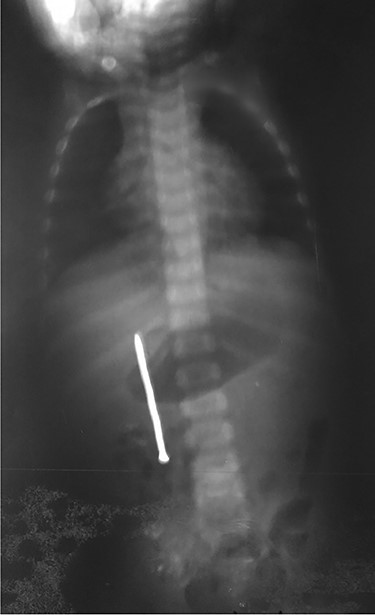

A 3-year-old male child was admitted in surgery department, with history of accidental ingestion of construction nail for 30 days, without any symptoms. Parents consulted in a peripheral hospital and plain abdominal radiography showed a nail projected in right-edge upon the lumbar spine (Fig. 1). Clinical observation was advised. The nail did not pass spontaneously and the child remained asymptomatic. Parents decided to consult again, but in our institution (surgery department). The child did not experience fever nor digestive symptoms (nausea, vomiting, abdominal pain, blood or color changes in stool). He had no prior history of FB ingestion.

Abdominal examination was normal. A repeat abdominal radiography was done. The nail’s position had not changed from the first X-ray site, with no free peritoneal air (Fig. 2).

Plain radiography plays the main role both in the diagnosis and the choice of operative interventional moment—either by pinpointing the radio-opaque image, or by showing certain FB characteristics, or by noting images suggesting complications (absent in our case), or even by projecting the FB in the same place over a period of time, an aspect inductive of fistula. In our case, right-edge superposition of the FB image upon the lumbar spine is characteristic of FB positioning in the second part of duodenum [5, 6]. Its persistence in the same place (the second part of the duodenum as in our case) suggests the presence of a duodenal fistula or perforation, which requires surgical intervention [7].